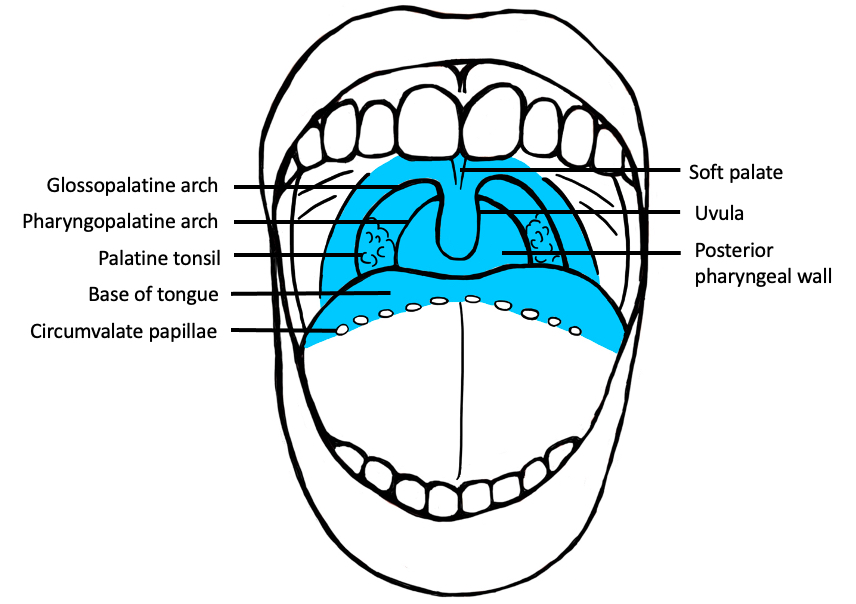

- Squamous cell carcinoma involving the oropharynx

- Oropharynx includes the soft palate, uvula, palatine tonsils, posterior third (base) of the tongue and posterior wall of the pharynx

Sites

- Oropharynx

- Most commonly soft palate